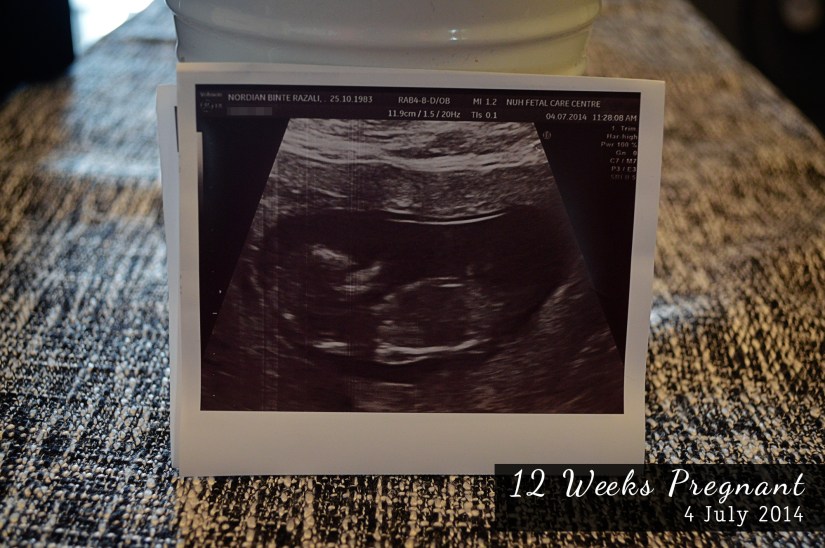

I was compiling all my Ultrasound scan pictures earlier and was amazed at how fast baby is growing.

12 Weeks

1 month later, we could see your limbs.